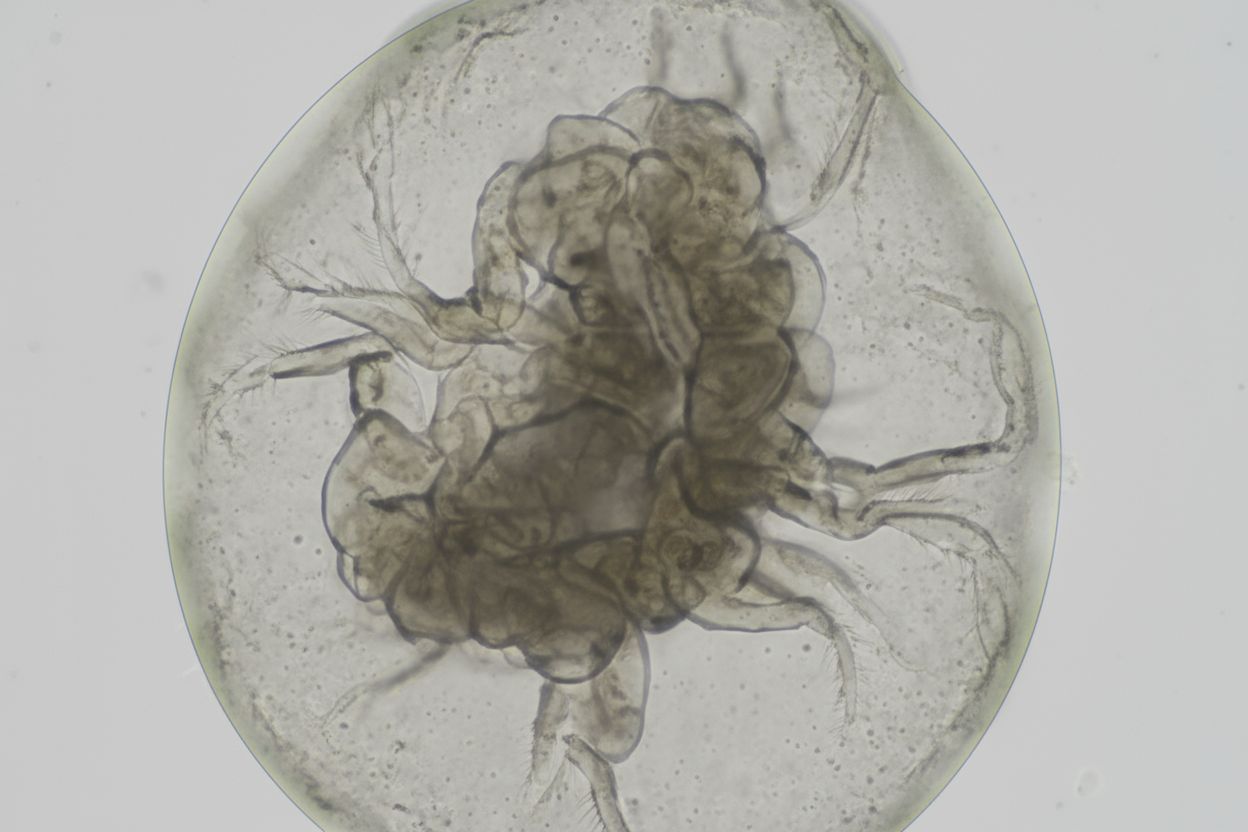

ORION | Advancing cancer treatment with personalized minitumors